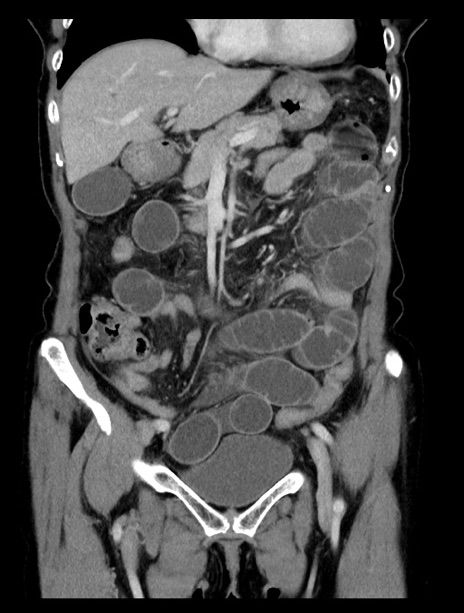

症例23(冠状断像)

【症例】70歳代女性

【主訴】下腹部痛・嘔吐

【現病歴】2日前より腹痛あり。昨日嘔吐あり。症状改善しないため来院。

【既往歴】胃GISTに対して胃部分切除後。

【身体所見】BT 37.1℃、BP 128/77mmHg、腹部:平坦・軟、下腹部に圧痛あり。

【データ】WBC 10200、CRP 0.31